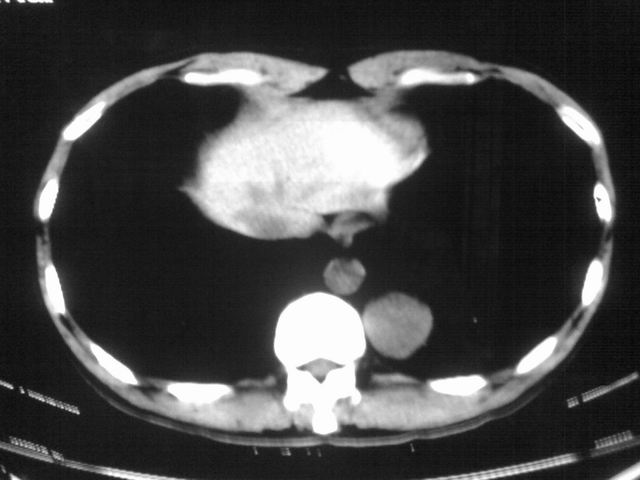

以下是引用苯小孩在2007-4-24 19:46:00的发言:[br]左下肺内侧基底段,见类圆形病灶,边缘清晰光滑.强化后轻中度强化.<平扫第4层面似有从腹主动脉相连血管影,可惜强化扫描这层没有抓住>考虑:左下肺隔离症.建议dsa或薄层强化重建观察.

以下是引用同在2007-4-24 20:11:00的发言:[br]考虑肺隔离症